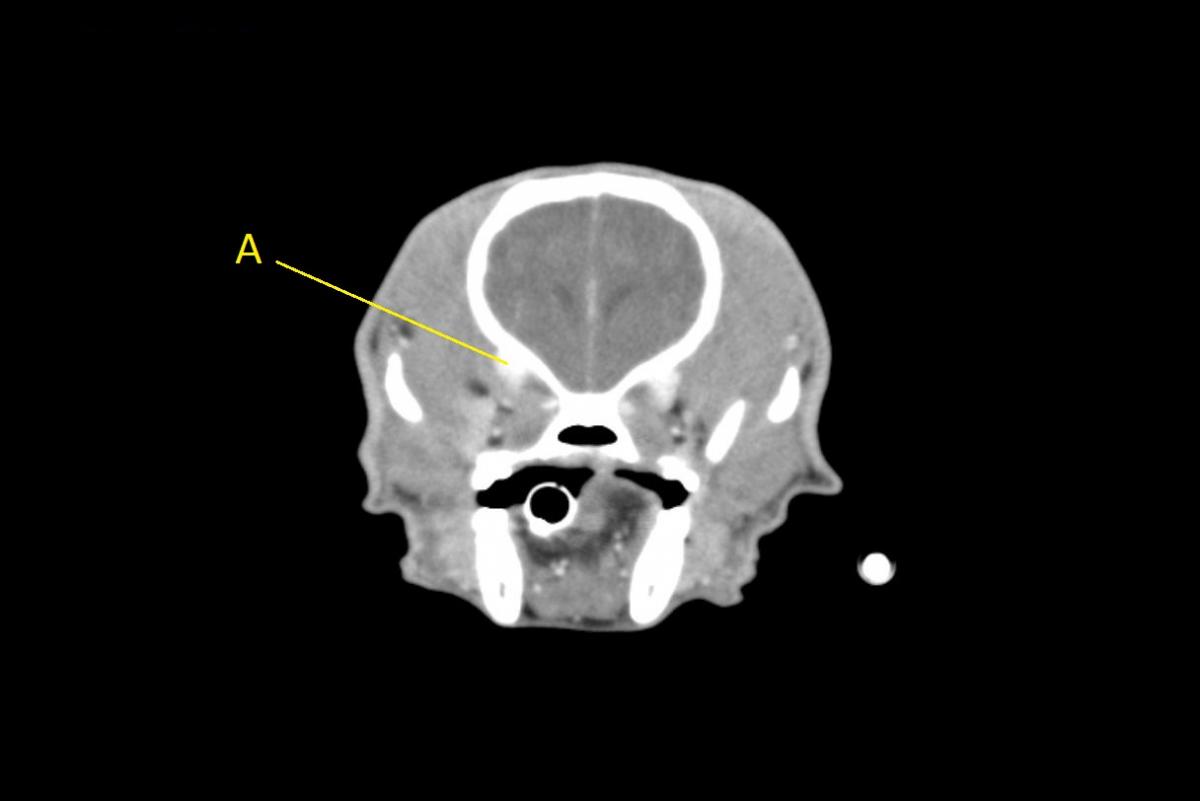

Q. Identify the structures labeled below:

A. ophthalmic venous plexus